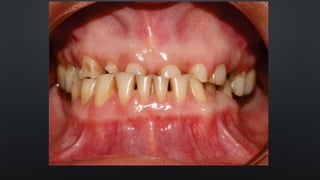

RELAÇÃO INTERDENTAL

• DISCREPÂNCIA MUSCULAR : DESLOCAMENTO DA POSIÇÃO NEUTRA

• HÁBITOS PARAFUNCIONAIS: CHUPAR DEDO, CACHIMBO, INSTRUMENTOS

MUSICAIS

• DISCREPÂNCIA MUSCULAR: DESLOCAMENTO DA POSIÇÃO NEUTRA RELAÇÃO INTERDENTAL

• HÁBITOS PARAFUNCIONAIS:CHUPAR DEDO, CACHIMBO, INSTRUMENTOS MUSICAIS RELAÇÃO INTERDENTAL